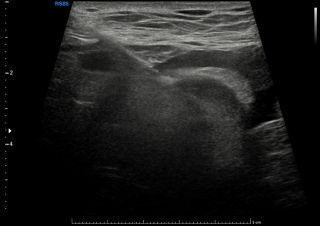

Case presentation

A 31-year-old previously healthy woman, with no surgical history, presented with sudden-onset, severe peri-umbilical abdominal pain unresponsive to high-dose opioids. CT-scan revealed mildly dilated distal jejunum with mesenteric edema and free fluid (Fig. 1, 2). Because of persistent pain despite step III analgesia, emergency diagnostic laparoscopy was performed. Intraoperatively, a closed-loop obstruction of an ileal segment was identified, herniated through a narrow internal window formed by an adherent mesenteric vessel supplying a Meckel’s diverticulum (Fig. 3). The vascular band was divided, releasing the closed loop, with no irreversible small bowel ischemic damage. The Meckel’s diverticulum was resected. The post-operative course was uneventful, and the patient was discharged after two days.